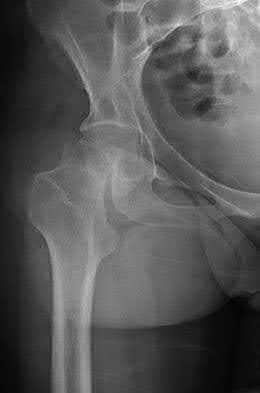

3. # Which of the following is not an appropriate implant for treatment of the fracture seen in Figure A?

The image shows a reverse obliquity intertrochanteric hip fracture.

According to the referenced article by Haidukewych et al, unstable peritrochanteric hip fractures have a worse outcome (failed in 9/16 cases) if treated with a sliding hip screw. Two additional factors that were found to have a strong correlation with postoperative failure (nonunion, loss of reduction) were poor reduction and poor implant placement. In this study, fixed angle devices were superior. Intramedullary fixation has the added advantage of a shorter lever arm and less potential for fracture collapse and limb shortening.

The IMN also acts as a medial buttress.

According to Sanders et al, the dynamic condylar screw (DCS) can also be used in subtrochanteric models, but should not be used if extensive comminution is seen, as they reported a high failure rate with DCS in these fractures if highly comminuted. They report a 77% overall union rate with this device.